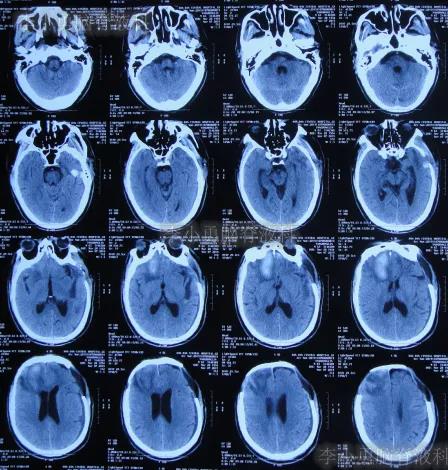

继续治疗1周时间内,曾3次复查头颅CT(图-5、图-6、图-7)均示脑膨出逐渐加重的趋势,仍有积血;期间给予腰大池引流。

图-5:2019年10月26日头颅CT

图-6:2019年10月29日头颅CT

图-7:2019年10月31日头颅CT

图-8:2019年11月3日头颅CT

开颅术后18天即2019年11月7日,脑膨出进一步好转(图-9)。

图-9:2019年11月7日头颅CT